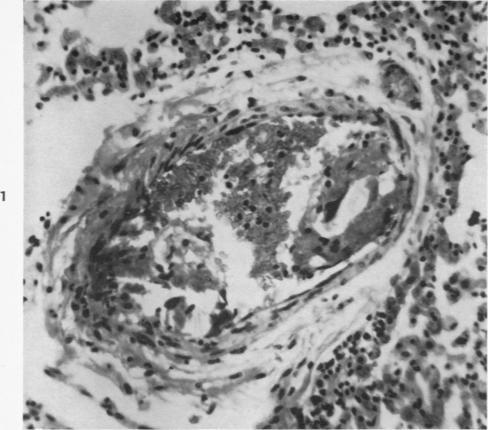

The reaction produced in the pulmonary arteries by emboli of cotton fibers.